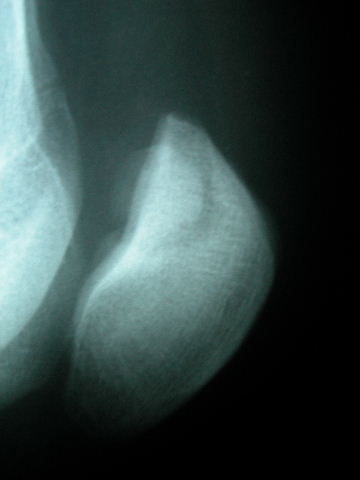

Prótesis completa de rodilla. Situación postquirúrgica.

Prótesis completa de rodilla. Situación postquirúrgica. Lateral.

Prótesis completa de rodilla.Lateral.

Prótesis completa de rodilla. Frontal.